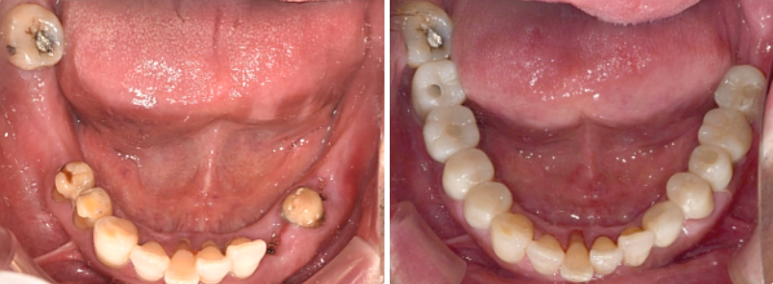

68세 남성 (보험 임플란트 포함)

(전) 2021-11-05, (후) 2022-08-26

임플란트/크라운 시술 후

음식 섭취뿐만 아니라, 심미적인 개선으로

삶의 질이 높아진 환자분의 사례